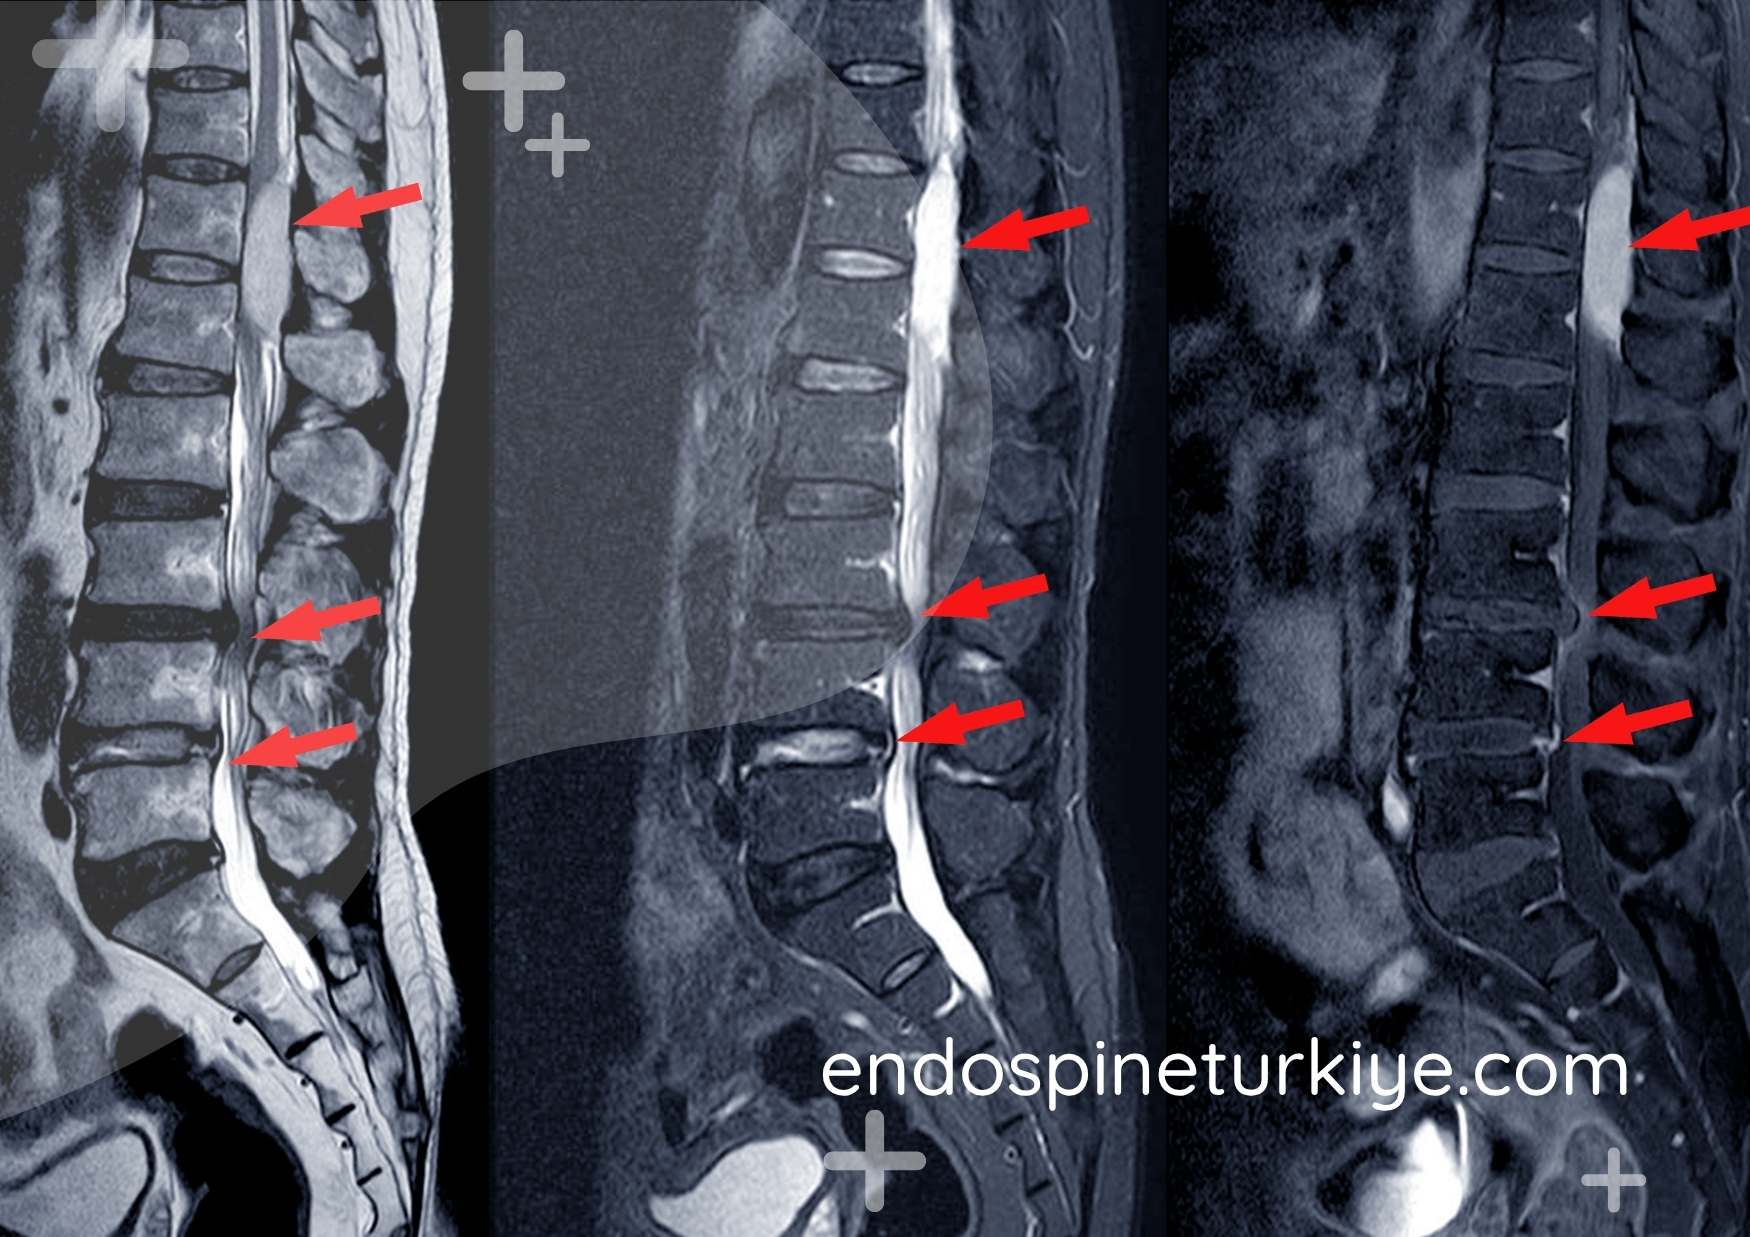

Lomber MR Bulguları

Normal lomber MR

Normal

Geniş spinal kanal

Dar kanal lomber MR

Dar Kanal

Belirgin daralma

Tipik MR Bulguları:

• Santral kanal AP çapı <10mm

• Trefoil (yonca yaprağı) görünümü

• Ligamentum flavum kalınlaşması

• Faset hipertrofisi